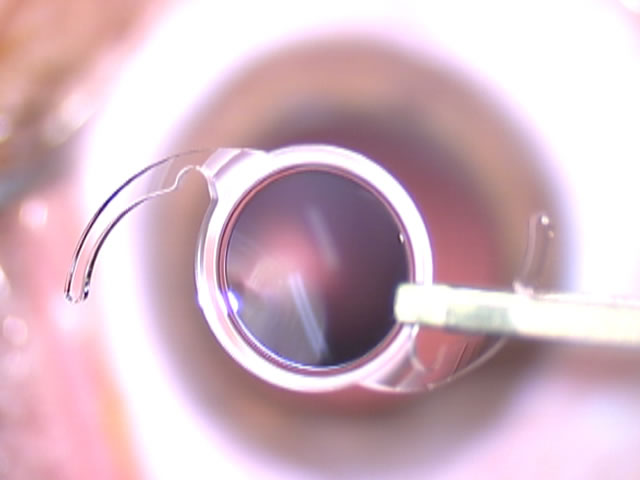

Presso il proprio studio di Gussago (Brescia), il dottor oculista Giovanni Coen esegue interventi di chirurgia refrattiva con impianto di lenti intraoculari asferiche Premium: una soluzione che permette la correzione dei difetti del cristallino (la seconda lente dell'occhio, situata internamente rispetto alla cornea) che, spesso anche per l'avanzare dell'età, perde la propria trasparenza causando una visione poco nitida e non definita. La microchirurgia del cristallino offre risultati eccellenti anche in presenza di cataratta e consente di eliminare difetti come la miopia, l'ipermetropia, la presbiopia e l'astigmatismo.

L'intervento consiste nella sostituzione, mediante laser, del cristallino danneggiato con lenti intraoculari artificiali mono o multifocali personalizzate, che garantiscono una visione perfettamente limpida, ad alto contrasto e priva di difetti. Il trattamento chirurgico è indolore anche nel post intervento, avviene tramite anestesia topica in gocce e permette l'immediata ripresa delle attività quotidiane in sole 24 ore.